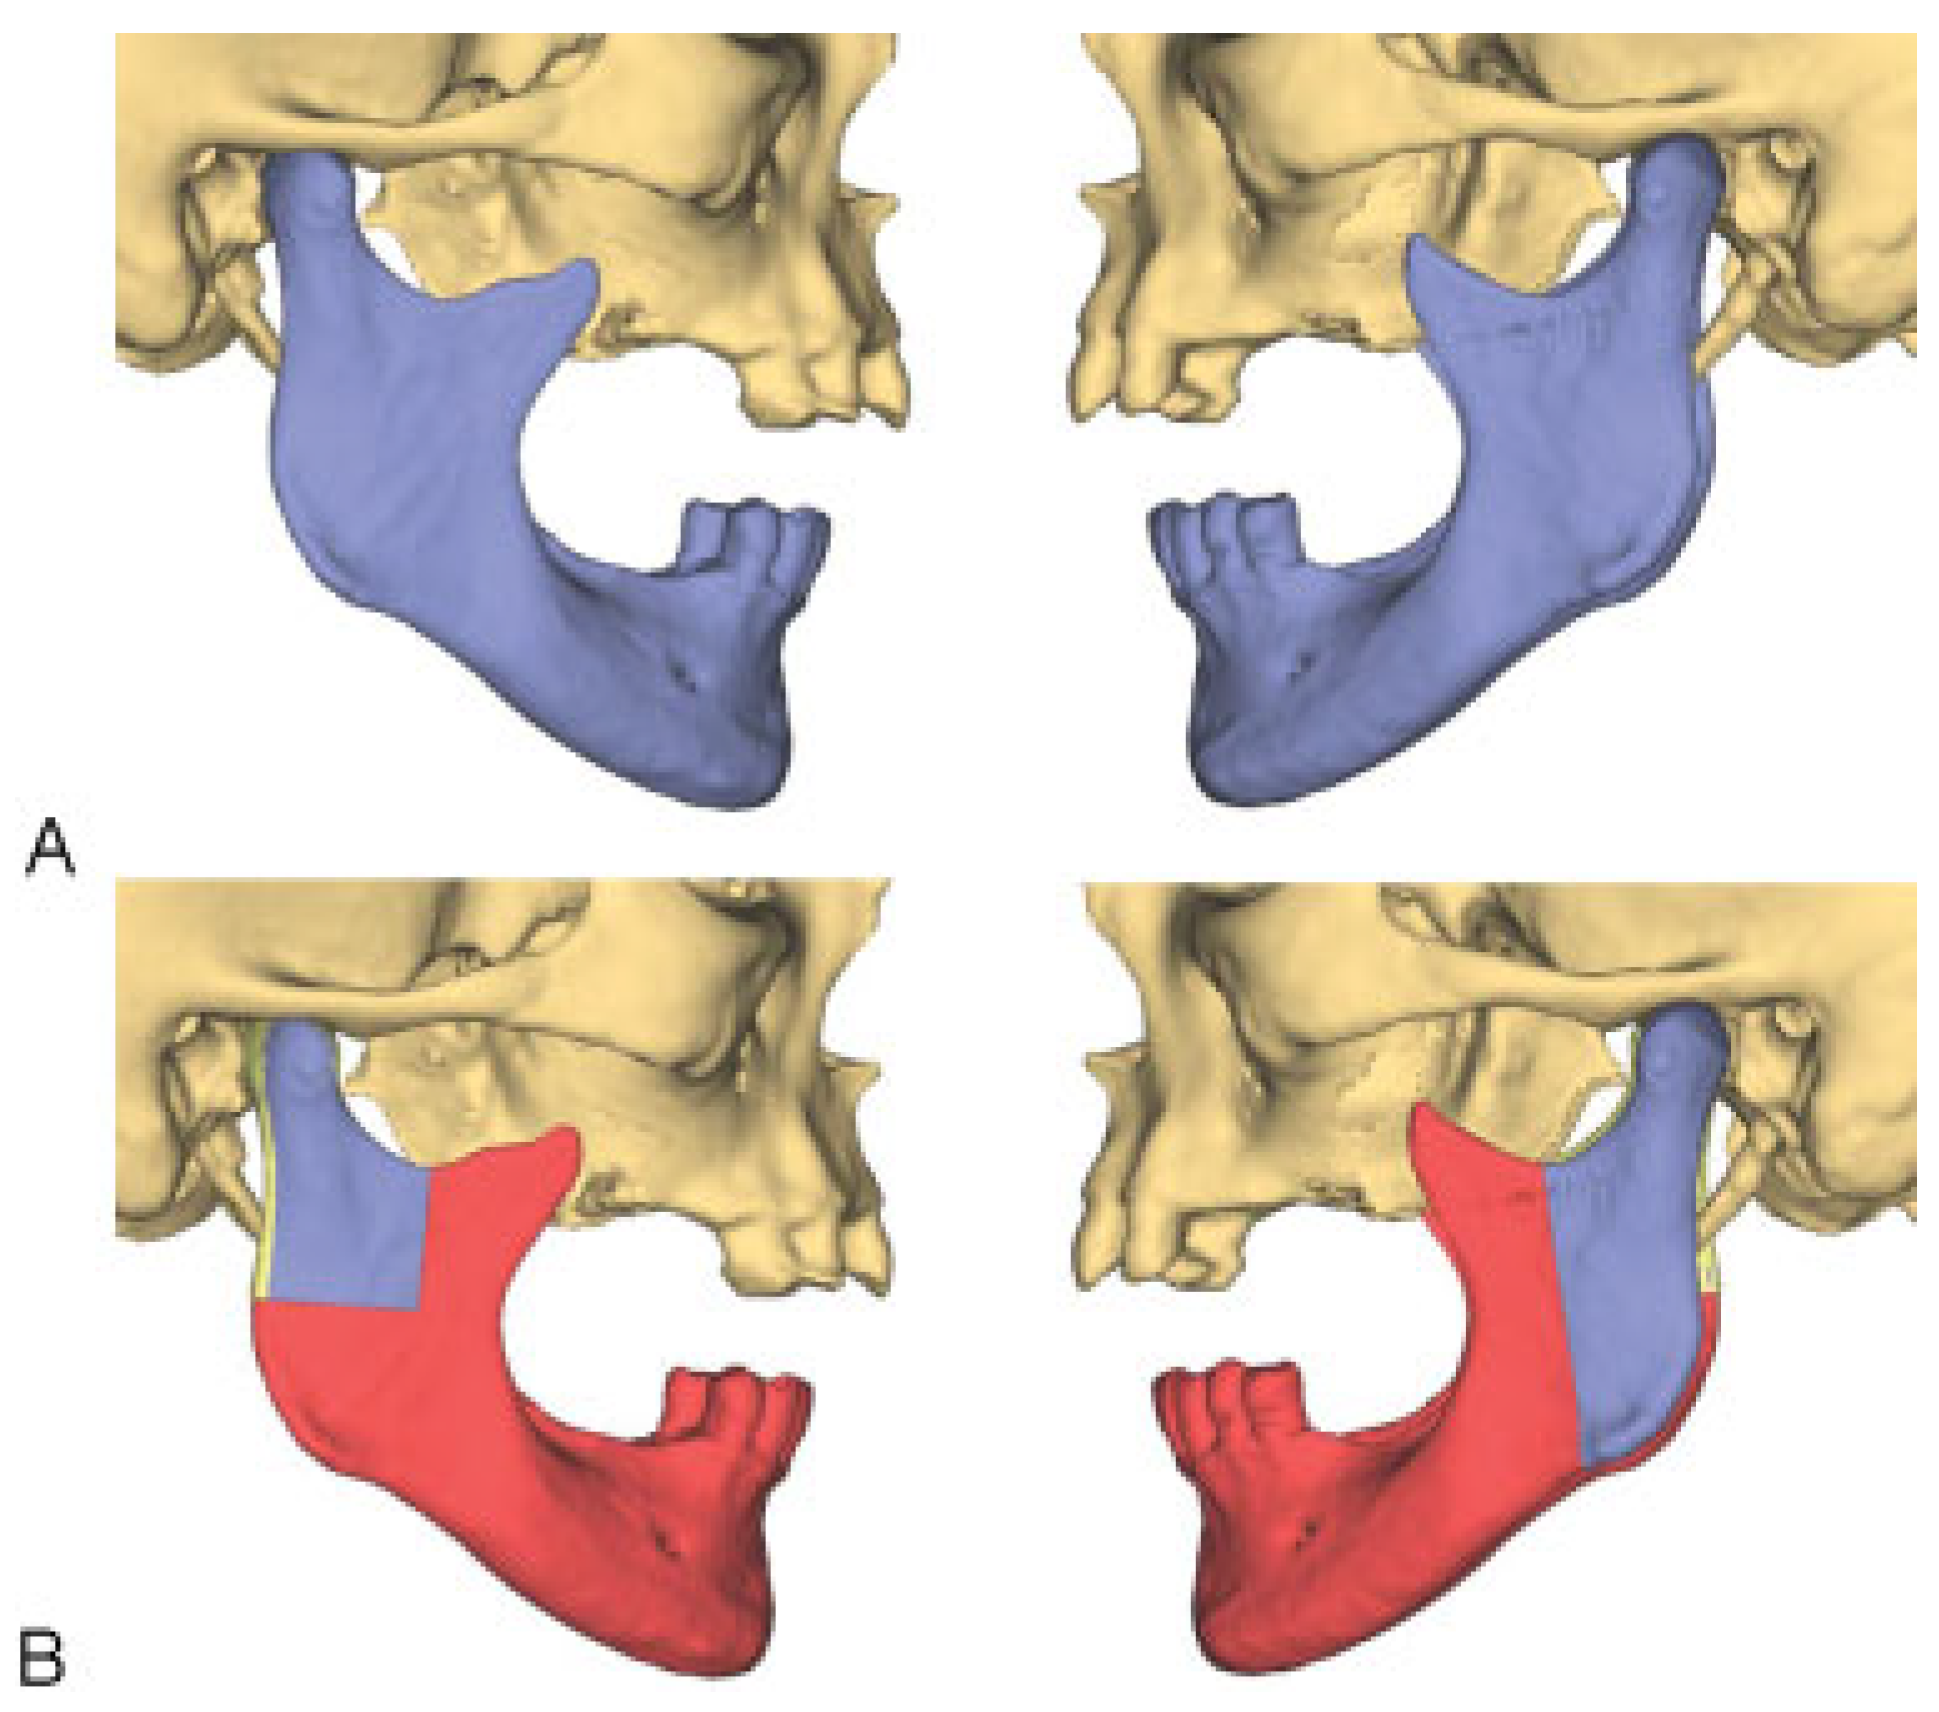

First, the resection planes of the mandible were established (Figure 2). The size of the mandibular segment that must be resected is usually determined by the extent of the pathology being treated. Clinical findings and especially diagnostic computed-tomography (CT) scans play a key role in this context.

Figure 2. Resection lines in the region of the mandible. (A) Mandible without resection (blue). (B) Planned resection (red) with preservation of the blue segments.